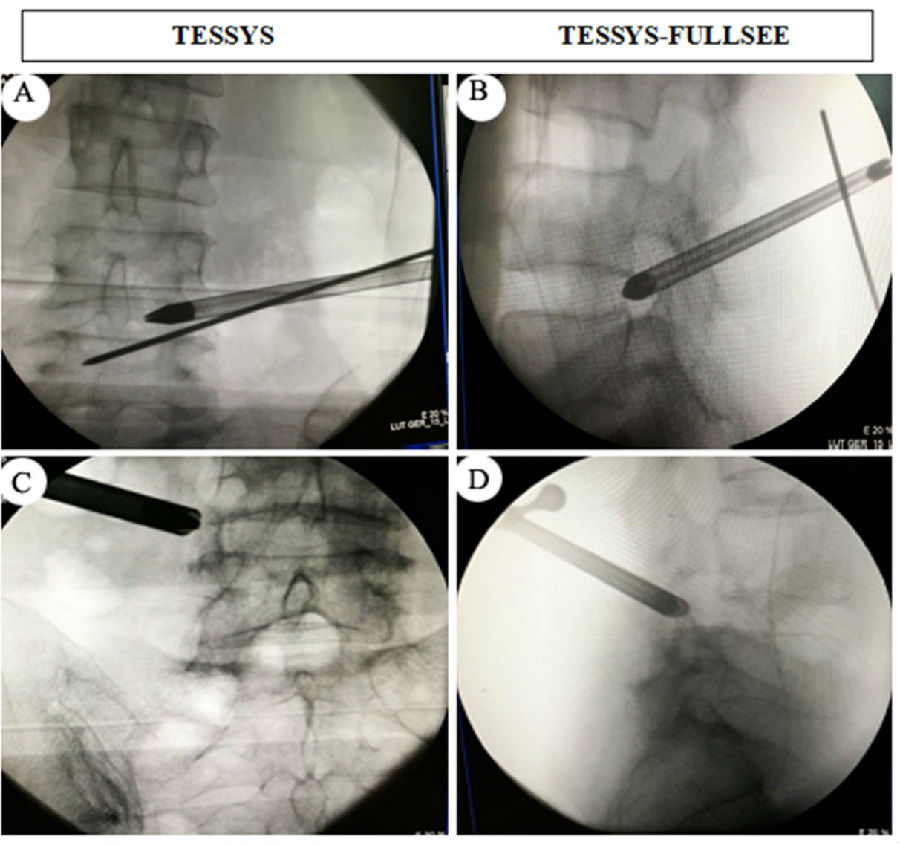

術(shù)中透視

與傳統(tǒng)的TESSYS技術(shù)穿刺全程需要X線透視相比,我們采用的全麻下的TESSYS-FULLSEE椎間孔鏡技術(shù),術(shù)中常規(guī)只需透視一次,然后在內(nèi)鏡可視化操作下將孔鏡工作套管置入病變區(qū)域。該技術(shù)具有以下特點:1. 真正意義上的全內(nèi)鏡技術(shù),貫穿穿刺至髓核摘除全過程;2.術(shù)中透視少,僅在將通道置入椎間孔后透視正側(cè)位一次,對病人和醫(yī)護(hù)人員輻射少;3.整個手術(shù)操作在脊柱內(nèi)鏡監(jiān)視下進(jìn)行,不易損傷神經(jīng),安全性好;4.采用全麻,病人舒適度高;5.與傳統(tǒng)脊柱內(nèi)鏡技術(shù)相比,精準(zhǔn)程度更高,組織創(chuàng)傷更小,減壓更徹底,術(shù)后疼痛緩解更明顯;局麻下手術(shù),患者術(shù)中可能會出現(xiàn)因神經(jīng)根刺激和髓核摘除操作給患者造成難以忍受的劇烈疼痛,術(shù)中需要靜脈輔助強(qiáng)化藥物來麻醉患者;這些弊病,全麻下可以完全避免。